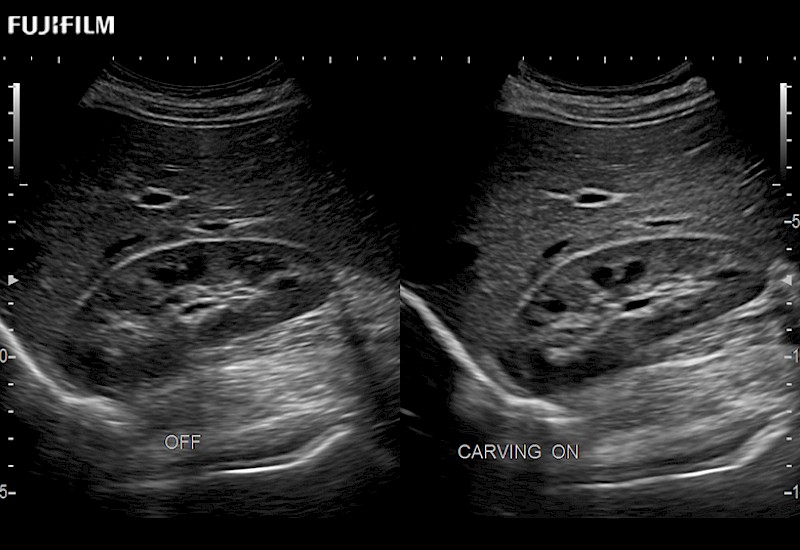

Extraordinary high-resolution digital imaging

Multi-Parametric imaging modalities

Our dedication to Surgical Oncology allows us to offer superior image quality, outstanding system reliability and intuitive use of cutting edge technology.